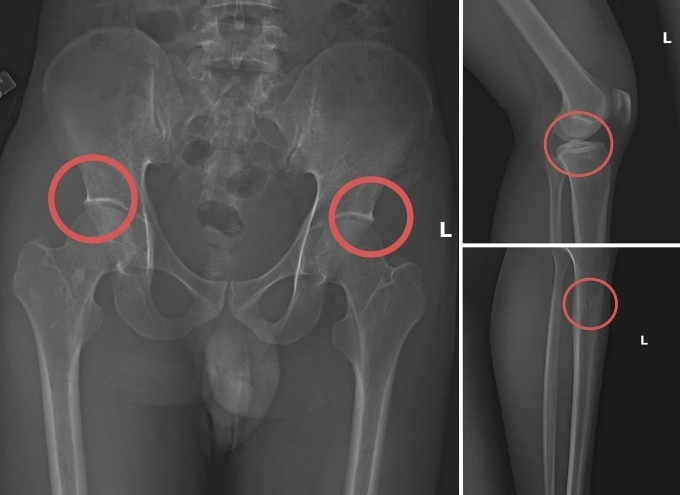

Các vết thương do Châu tự tạo nên. Ảnh: Công an cung cấp

Tại đây,anh ta tiêm thuốc mê vào tĩnh mạch tay phải của người mua bảo hiểm để họ hôn mê. Sau đó,Châu dùng búa và kim tiêm đục,đâm vào vùng cơ thể đã thống nhất từ trước để tạo vết tổn thương trên xương cho nứt,vỡ. Thông thường,Châu sẽ làm rạn nứt,vỡ vùng xương chậu,đùi.